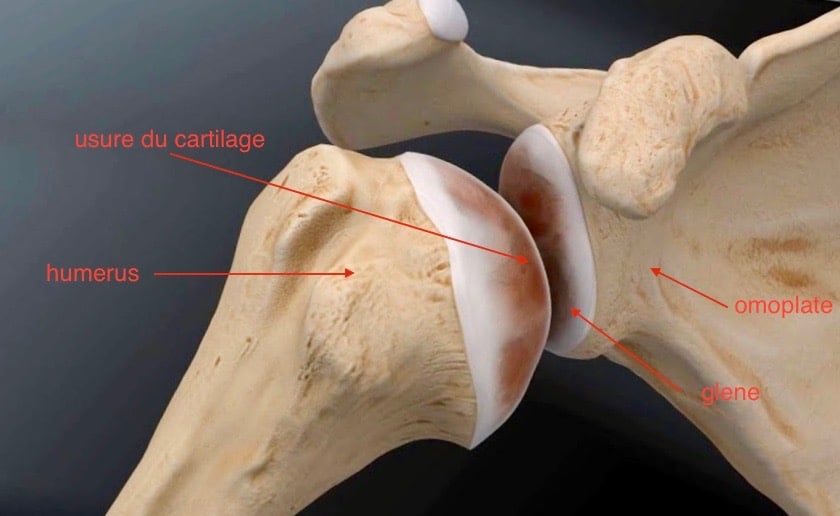

L’omarthrose est une usure du cartilage de la tête humérale et de la glène de l’omoplate. Usure naturelle ou faisant suite à un traumatisme, l’omarthrose est parfois associée à des lésions des tendons de la coiffe des rotateurs.

La douleur ressentie est parfois assortie d’un enraidissement c'est-à -dire d’une diminution progressive de la mobilité.

La radiographie de l’épaule met en évidence un pincement de l’interligne articulaire et une production d’os (ostéophytes) autour de la tête de l’humérus, apparaissant comme une goutte.

Omarthrose centrée

Omarthrose excentrée